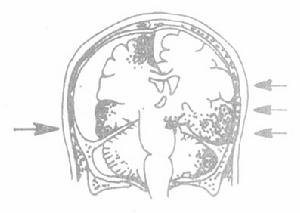

2.閉合性腦損傷 閉合性腦損傷的手術主要是針對顱內血腫或重度腦挫裂傷合併腦水腫引起的顱內壓增高和腦疝,其次為顱內血腫引起的局灶性腦損害。 由於CT檢查在臨床診斷和觀察中廣泛套用,已改變了以往的“血腫即是手術指征”的觀點。一部分顱內血腫病人,在有嚴格觀察及特殊監測的條件下,套用脫水等非手術治療,可取得良好療效。顱內血腫可暫不手術的指征為:無意識障礙或顱內壓增高症狀,或雖有意識障礙或顱內壓增高症狀但已見明顯減輕好轉;無局灶性腦損害體徵;且CF檢查所見血腫不大(幕上者40m1,幕下者>10m]),或血腫雖不大但中線結構移位明顯(移位>lcm)、腦室或腦池受壓明顯者;⑤在非手術治療過程中病情惡化者。顳葉血腫因易導致小腦幕切跡疝。手術指征應放寬;硬腦膜外血腫因不易吸收,也應放寬手術指征。 重度腦挫裂傷合併腦水腫的手術指征為:①意識障礙進行性加重或已有一側瞳孔散大的腦疝表現;②CT檢查發現中線結構明顯移位、腦室明顯受壓;③在脫水等治療過程中病情惡化者。凡有手術指征者皆應及時手術,以便儘早地去除顱內壓增高的病因和解除腦受壓。已經出現一側瞳孔散大的小腦幕切跡疝徵象時,更應力爭在30分鐘或最遲1小時以內將血腫清除或去骨瓣減壓;超過3小時者,將產生嚴重後果。 常用的手術方式有:

3.鑽孔探查術 已具備傷後意識障礙進行性加重或出現再昏迷等手術指征,因條件限制術前未能作CT檢查,或就診時腦疝已十分明顯.已無時間作CT檢查,鑽孔探查術是有效的診斷和搶救措施。鑽孔在瞳孔首先擴大的一側開始,或根據神經系體徵、頭皮傷痕、顱骨骨折的部位來選擇;多數鑽孔探查需在兩側多處進行。通常先在顳前部(翼點)鑽孔,如未發現血腫或疑其他部位還有血腫,則依次在額頂部、眉弓上方、顳後部以及枕下部分別鑽孔。注意鑽孔處有無骨折,如鑽透顱骨後即見血凝塊,為硬腦膜外血腫;如未見血腫則稍擴大骨孔,以便切開硬腦膜尋找硬腦膜下血腫,作腦穿刺或腦室穿刺,尋找腦內或腦室內血腫。發現血腫後即作較大的骨瓣或擴大骨孔以便清除血腫和止血;在大多數情況下,須敞開硬腦膜並去骨瓣減壓,以減輕術後腦水腫引起的顱內壓增高。